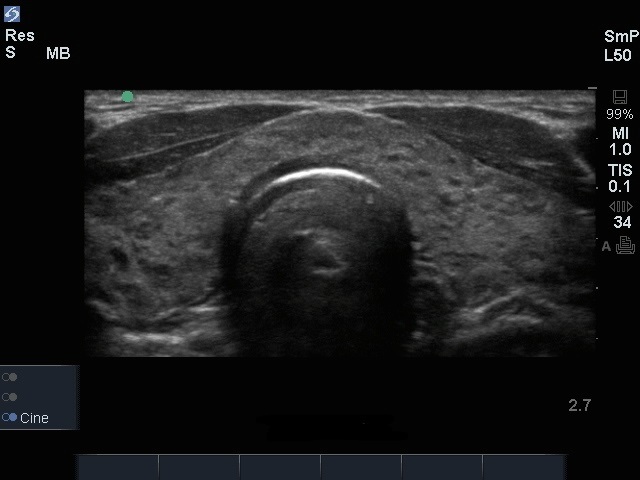

甲状腺异常横切面图像